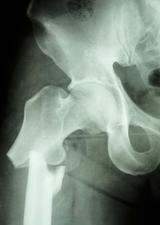

Researcher studies rare fractures in post-menopausal women

Researchers in the Faculty of Kinesiology and the McCaig Institute for Bone and Joint Health are studying the cause of these fatigue fractures, known as atypical femoral fractures that occur in the thighbone, to help prevent this injury.